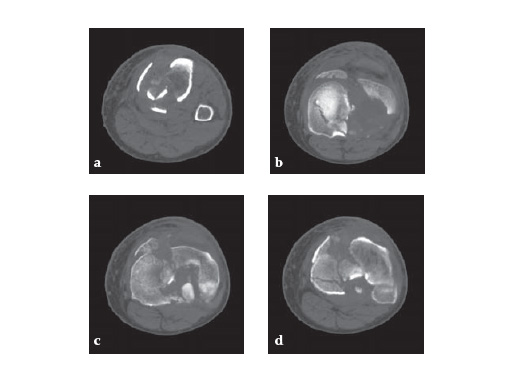

57-year-old malemotor accident

Case provided by Phil Kregor, Nashville, USA